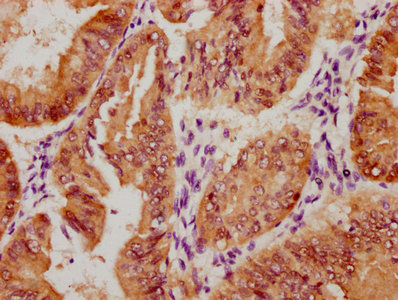

The image on the left is immunohistochemistry of paraffin-embedded Human brain tissue using CSB-PA297945(KRT13 Antibody) at dilution 1/35, on the right is treated with fusion protein. (Original magnification: ×200)

The image on the left is immunohistochemistry of paraffin-embedded Human cervical cancer tissue using CSB-PA297945(KRT13 Antibody) at dilution 1/35, on the right is treated with fusion protein. (Original magnification: ×200)